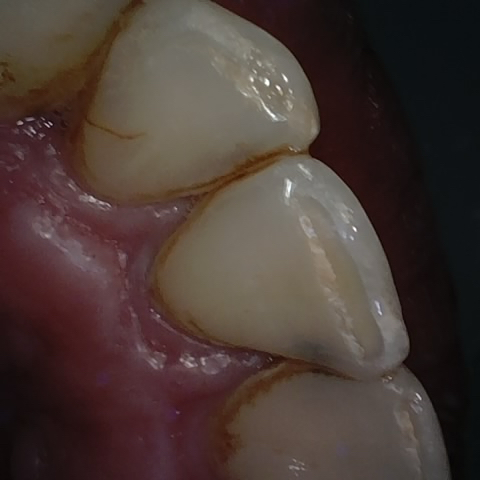

Annotated as "Good"